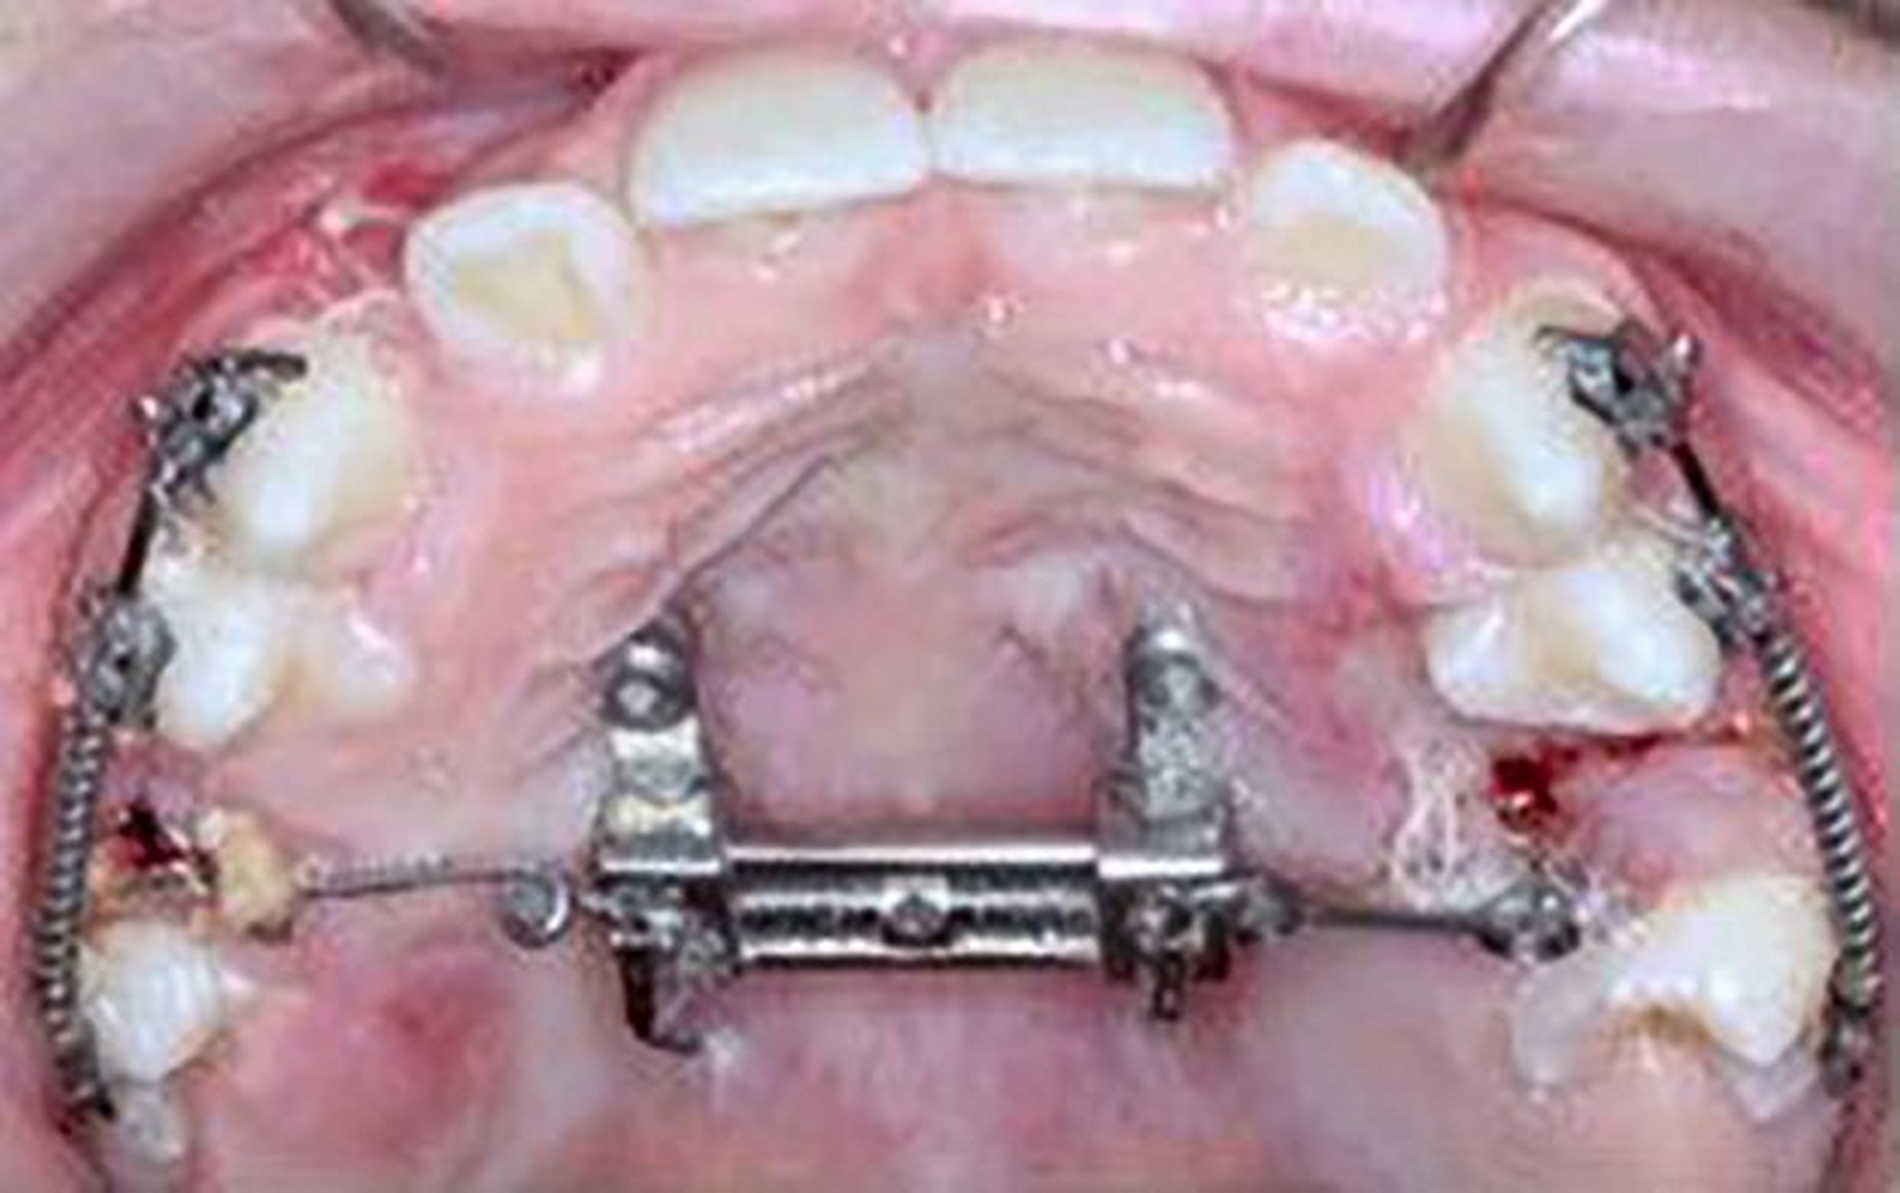

Die Zähne 36, 37, 46 und 47 wurden in Allgemeinanästhesie chirurgisch freigelegt. Zusätzlich wurden die beiden paramedianen Mini-Implantate (2 x 9 mm, Benefit System; PSM North America, Indio, CA) ohne Vorbohren mithilfe der zuvor hergestellten Schablone inseriert (Abbildung 3). Für die Platzierung der Mini-Implantate wurde ein Winkelschraubendreher verwendet. Direkt nach der Operation wurde die bmx DIRECT Hyrax-Schraube (10 mm, BENEfit®-System, Dentalline, Birkenfeld, Deutschland) an den Mini-Implantaten befestigt, um ein MARPE zu erzielen (Abbildung 4).

Die Eltern des Patienten wurden angewiesen, die Schraube einmal täglich zu aktivieren. Die gesamte Aktivierungszeit der Hyrax-Schraube betrug circa zehn Wochen. Während dieser Zeit vergrößerte sich die transversale Dimension des Oberkiefers um sieben Millimeter im posterioren Bereich (Milchmolaren) und um fünf Millimeter im anterioren Bereich (Milcheckzähne). Währenddessen trat ein mediales Diastema auf (Abbildungen 4b und 4c), das auf eine skelettale transversale Expansion des Oberkieferknochens hinwies. Nach der aktiven Expansionsphase der Hyrax-Apparatur wurde das Gerät für weitere Behandlungszwecke verwendet: Erstens als Retentionsgerät, um die bereits erzielte transversale Oberkieferbreite zu halten und zweitens als skelettal verankerte Apparatur zum Einstellen der retinierten und verlagerten Zähne mithilfe individuell angefertigter Kragarme. Hierfür wurde die Hyrax-Apparatur im zahntechnischen Labor modifiziert, indem Kreuzröhrchen für eine stationäre Befestigungen für die Drähte des Kragarms angebracht wurden.

Für die Zähne 13, 16, 23 und 26 wurde eine weitere chirurgische Freilegung durchgeführt. Zwei Kragarme (0,017 x 0,025 Zoll TMA-Draht, Dentaurum, Ispringen, Deutschland) wurden verwendet, um die Zähne 13 und 23 kieferorthopädisch in den Zahnbogen einzustellen. Danach wurde eine Teil-Multi-Bracket-Apparatur eingesetzt, um die eruptierten Zähne zu nivellieren (Abbildung 5b). Nach einer Behandlungsdauer von circa sechs Monaten waren die chirurgisch freigelegten Zähne optimal eingeordnet (Abbildungen 5c und 5d). Um die Lücke für die noch retinierten Prämolaren 15 und 25 zu öffnen, wurden in dieser Region auf den Teilbögen offene Federn angebracht. Danach wurden die Zähne 15 und 25 chirurgisch freigelegt und ebenfalls mithilfe von zwei Kragarmen (0,017 x 0,025 Zoll TMA-Draht) eingestellt (Abbildungen 5e und 5f, Abbildung 6).